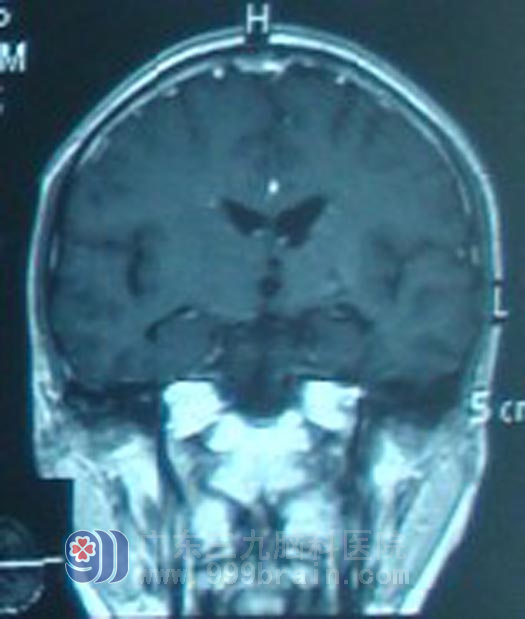

为求进一步治疗,当即赶到广东三九脑科医院就求医。入院后,医生结合影像及症状、血清肿瘤标记物等检查综合考虑为生殖细胞瘤可能性大。在征得阿军及其家属同意后,予以诊断性放疗。放疗10Gy后复查显示阿军的肿瘤明显缩小。遂进一步确诊为生殖细胞瘤。继续予头颅放疗及全脊髓预防照射。放疗后阿军一直遵医嘱定时化疗及复查,5年来未见肿瘤复发征象。前日阿军女朋友陪阿军来复查,影像未见肿瘤复发,生活状态如正常人。

广东三九脑科医院肿瘤综合治疗中心蔡林波主任介绍:颅脑生殖细胞瘤的是治疗预后良好的恶性肿瘤,阿军治疗后已近5年,5年未见复发转移征象,称为临床治愈,乐观的是,经治疗后,脑肿瘤基本没有给阿军留下后遗症,5年来他如正常人般生活和工作。但蔡林波主任同时指出,对于阿军来说,仍需要关注自身身体健康状况,如遇不适,及时就诊。同时也提醒大家,及时的就医观念,积极配合医生治疗,积极乐观的心态对疾病的预后都有重要的影响。http://www.999brain.com/

治疗后5年